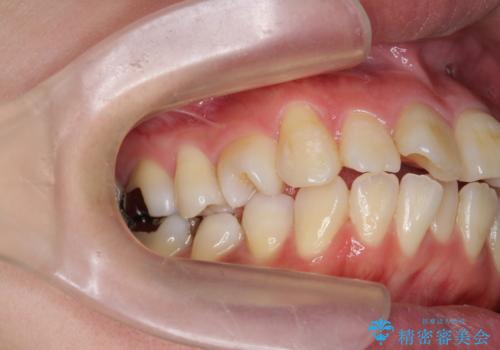

捻れた奥歯 突き出た前歯を治したい

- 出っ歯に見える前歯、捻れてしまった小臼歯の改善を求めて来院されました。

マウスピースでは改善の難しい小臼歯のねじれをまず部分ワイヤー矯正で改善し、その後マウスピース矯正で前歯の突出感を改善します。

時間はかかりましたが、捻れ、かみ合わせ、前歯の角度の改善が達成され満足いただくことができました。